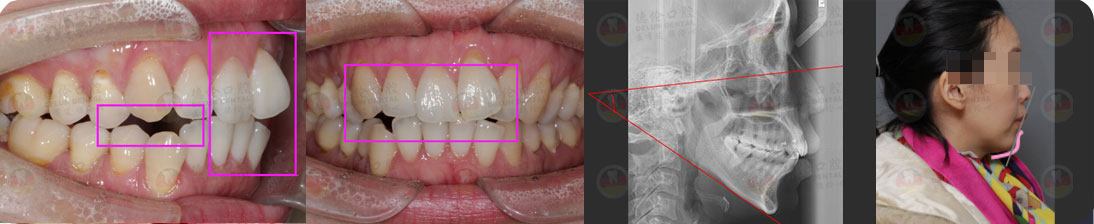

德倫口腔矯正診室指定專家團是以德倫口腔總院正畸科主任、時代天使全國智美隱形矯治病例大賽三等獎得主――熊小琴主任,和德倫口腔總院正畸科資深專家、隱形矯正培訓講師、有 26 年口腔醫療臨床經驗的王蘇靜醫生,共同領銜的 16 位隱形正畸認證醫師。指定專家團實力雄厚,臨床經驗豐富,內含多名口腔正畸專業博士、碩士組成的正畸博碩專家團和第 18 屆雅加達亞運會中國代表團時代天使口腔保障營專家團。